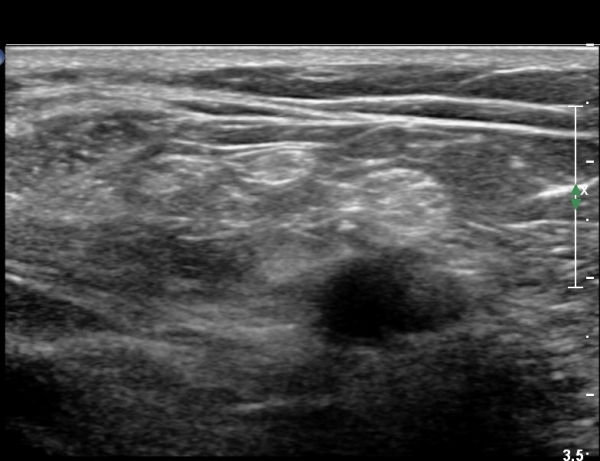

ŽÃËÀÚ¸¦ Á» ´õ ¸»´Ü, ¿ÜÃøÀ¸·Î À̵¿ÇÏ´Ï ºñ°ñµÎ Ç¥Ãþ¿¡¼­ ºñ°ñ½Å°æÀÌ Àú¿¡ÄÚ·Î °üÂûµÈ´Ù(»çÁø 3, 4, 5).